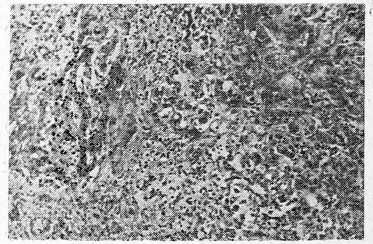

Упитанность значительно понижена. В полости перикарда 700 мл геморрагической жидкости. Эпикард сплошь покрыт ворсинистой пленкой фибрина. Под ней на месте эпикарда видна бело-серая ткань, покрывающая все сердце в виде панциря (см. рис. 1).

Рис. 1. Между мощным слоем фибрина и миокардом светлая полоса опухолевой ткани. Вверху видны прорастание ею ушка предсердия и замурованная в ней коронарная артерия. Макропрепарат.